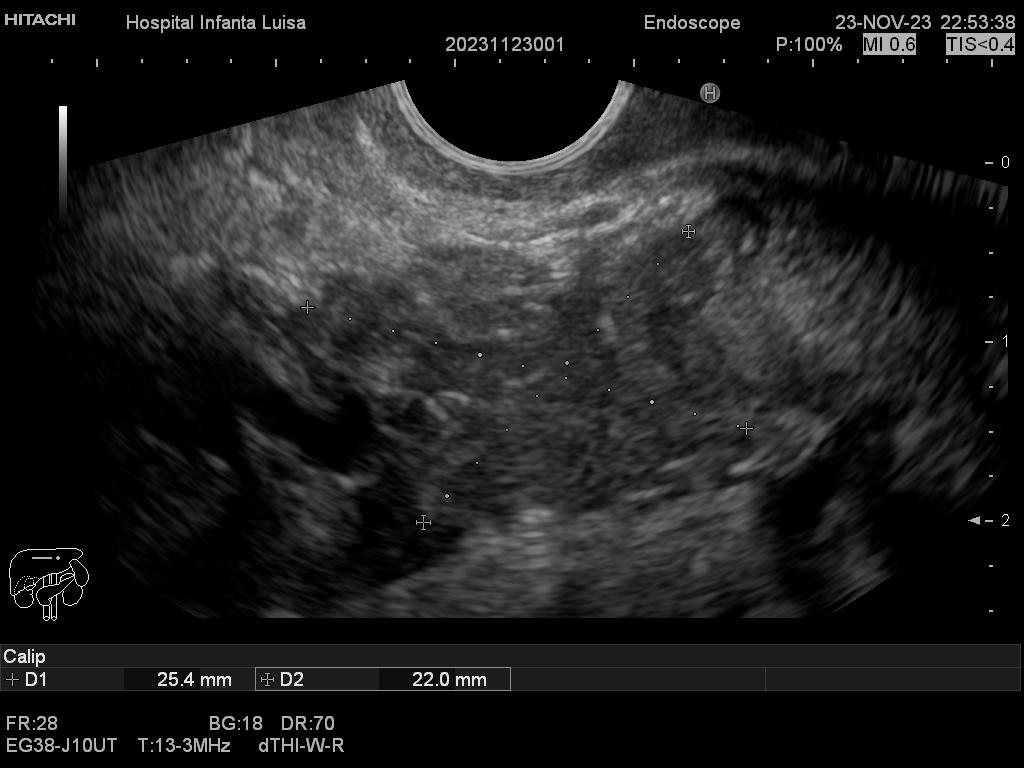

La Ecoendoscopia o Ultrasonografía endoscópica (USE) consiste en la exploración del tracto digestivo superior (principalmente), o de los últimos centímetros del tracto digestivo inferior (recto, generalmente), con un tipo de endoscopio especial que se llama ecoendoscopio.

La Ecoendoscopia, como su nombre indica, combina dos tipos de técnicas: la endoscopia y la ecografía, pues nos aporta simultáneamente una visión endoscópica (similar, aunque no igual, a la alcanzada con el gastroscopio y el colonoscopio) y ecográfica, que permite la visualización y estudio de las estructuras que quedan por fuera y están en contacto con la pared del esófago, estómago, duodeno o colon.

Mediante dicha exploración se explora minuciosamente los tramos mencionados, permitiendo valorar distintas patologías como lesiones propias de la pared de estos órganos (determinado su profundidad y extensión), o lesiones que quedan en órganos anexos, pero por fuera, de ahí la importancia de la visualización ecográfica, como páncreas, mediastino, hígado, diferentes adenopatías o masas indeterminadas previamente, entre otros.

Igualmente, es una técnica básica hoy día en el estudio de todo tipo de lesiones pancreáticas, en la determinación de formaciones subepiteliales esofágicas, gástricas (más frecuentes) o duodenales, o en el estadiaje de patología tumoral a estos niveles. La Ecoendoscopia permite la toma de biopsias a estos niveles, con control endoscópico y ecográfico, siendo una técnica de gran rentabilidad diagnóstica y seguridad.